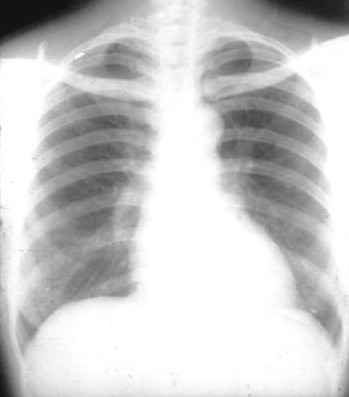

照片名称:正常胸片